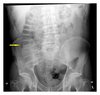

74

What might you see on AXR of neonate with NEC?

* Dilated bowel loops * Bowel oedema/thickened bowel wall * **Pneumatosis intestinalis** *(gas in bowel wall)* * Pneumoperitoneum *(indicates perforation)* * Gas in portal veins